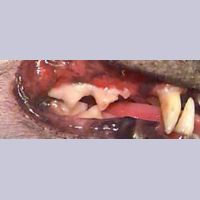

Image 7.12. Lymphocytic Plasmacytic

송곳니와 작은 어금니 주변의 염증

고양이과 Lymphocytic Plasmacytic 증후군